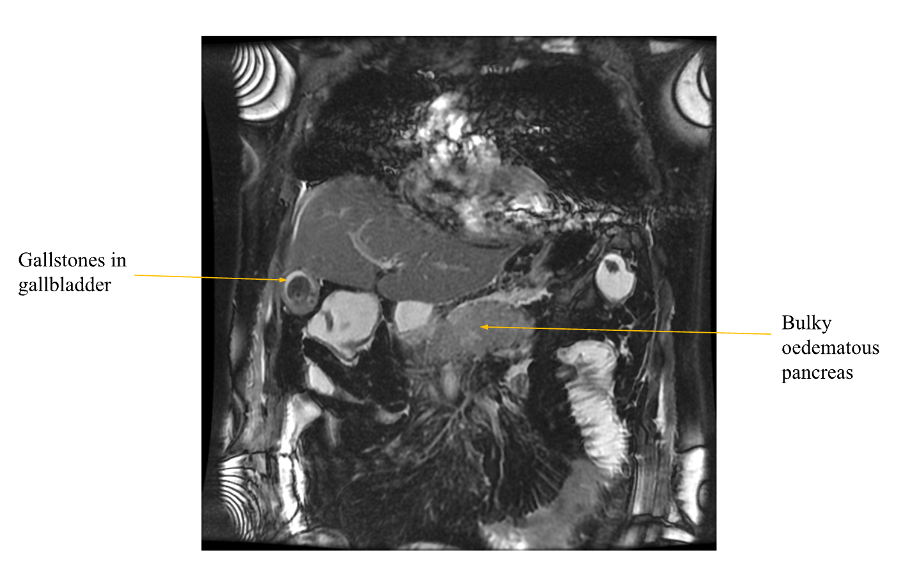

Magnetic Resonance Cholangiopancreatography (MRCP)

- MRCP may be useful in cases of diagnostic uncertainty, or where choledocholithiasis (gallstones in the CBD) or pancreatic stones are suspected e.g. with CBD/pancreatic duct dilatation. Can also be used to identify potentially malignant HPB lesions which may be obstructing, and when planning ERCP.

Acute pancreatitis (MRCP)

Case courtesy of Mohamed AbdelBar, Radiopaedia.org, rID: 76283